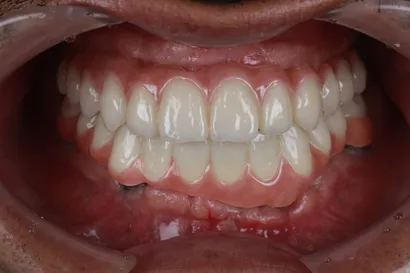

重度虫歯からの全顎インプラント治療

40代 男性

執刀医 Dr.大杉 治療内容 1回の手術でインプラントを埋め込み、即時の仮歯を装着して早期の機能回復を図りました。その後、噛み合わせを調整し、セラミックの製作を行いました。

上顎:ピンクポーセレンを用いたフルジルコニアインプラントブリッジ(All-on-4)

下顎:ピンクポーセレンを用いたフルジルコニアインプラントブリッジ(All-on-4)治療期間 1年 費用 上顎:330万 税抜

下顎:330万 税抜リスク 術後、硬い物を食べないでください。インプラントが骨に結合するまで2ヶ月かかります。この期間中に強い負荷をかけると、結合しないことがあります。 -